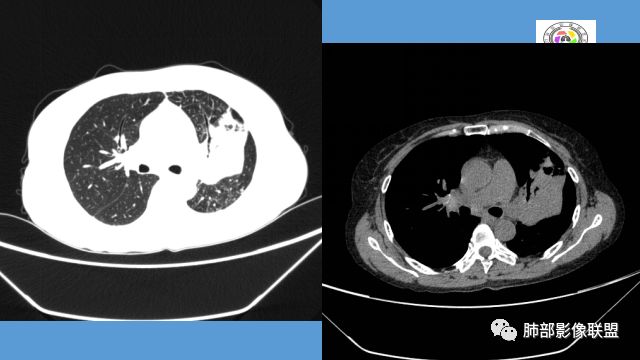

中年女性,反复咳嗽咳痰4月。胸CT:左肺上叶块状病变,病灶内可见支气管征,边缘见棘突样改变,周围可见结节状卫星灶,纵隔可见淋巴结肿大,部分淋巴结可见钙化灶。增强CT病灶内可见低密度坏死区。病灶整体呈收缩,考虑为良性病变,结核可能性大,建议支气管镜检查。

左肺病变支气管有狭窄后扩张,有部分钙化,符合结核,但叶间裂有膨隆,支气管有受压变窄表现,部分病灶内有血管,不能排除腺癌的可能,所以考虑肺结核合并腺癌可能

中年女性,咳嗽咳痰4月,加重半月。偶发热,肿瘤指标升高。病变主要位于左肺上叶后部,实变,病灶大部边缘平直、局部膨隆,邻近叶间裂局部向后膨隆,病变密度整体较均匀,见小斑片状低密度区及点状钙化影;左肺上叶舌段支气管可疑截断,病灶内支气管走形迂曲变形、不规则狭窄扩张、部分支气管内粘液栓形成,可见局部扩张支气管似小空洞相连,病灶内血管走形自然;糊墙。病灶前缘小叶间隔增厚,平滑;左肺下叶支气管管壁增厚,见部分树芽征及腺泡结节,边缘不清。纵膈及双肺门部分淋巴结钙化,隆突下淋巴结增大;未见胸腔积液。1.左肺上叶病灶倾向于恶性肿瘤,腺癌可能,排除粘液腺癌;2.左肺下叶少许炎症;

左上肺片状高密度影,其内有充气支气管征,血管造影征,叶间裂明显膨隆,支持粘液腺癌,鉴别于淋巴瘤、结核

左上胸缩小,但是左上叶部分实变,边缘膨隆,内部有含气支气管,粘液栓,近端支气管堵塞

前端支气管通畅,部分稍扩张,走形自然

实变区支气管内粘液栓明显

上叶支气管堵塞处稍萎缩、凹陷,附近壁增厚,内可见小点状钙化

2.左肺上叶大片实变影,密度不均,体积轻度增大,注意轻到中度强化及血管影未见破坏、未见坏死空洞……病灶更符合炎症,而不大支持干酪性结核及肺鳞癌等,后两者的破坏能力是比较强的。

3.支气管阻塞,沿途可见钙化及液性潴留……更符合支气管内膜结核。

综上,双肺继发性肺结核诊断应当成立;左肺上叶大片影,以支气管内膜结核伴阻塞性炎症解释更为合理。